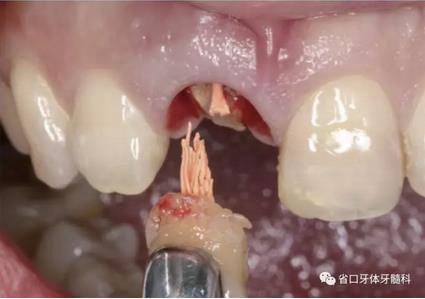

(1)微創(chuàng)拔牙及即刻種植:術(shù)前拍攝口內(nèi)照及實(shí)施牙周基礎(chǔ)治療。常 規(guī)消毒鋪巾阿替卡因局麻下微創(chuàng)拔除上頜右側(cè)中切牙,搔刮拔牙窩及根尖肉 芽組織。探測牙槽骨唇側(cè)骨壁及鄰面牙槽嵴完整,牙齦無撕裂。不翻瓣下于上頜右側(cè)中切牙缺隙近遠(yuǎn)中中點(diǎn)的腭側(cè)牙槽骨及根方定位,按照逐級預(yù)備的原則,緊貼牙槽窩腭側(cè)骨壁制備種植窩洞,植入Zimer®3.7mm×13mm TSV種植體1顆,植入扭矩>35N·cm,以O(shè)sstell測量種植體的ISQ值為68。 種植體平臺(tái)位于唇側(cè)齦緣中點(diǎn)下3mm,與唇側(cè)骨壁內(nèi)側(cè)面形成的跳躍間 隙約2mm,置入Bio-Oss®細(xì)顆粒骨粉0.25g,上愈合基臺(tái)關(guān)閉創(chuàng)口。術(shù)后 CBCT檢查顯示:種植體利用牙槽窩根方骨質(zhì)固位,緊貼牙槽窩腭側(cè)骨壁, 其唇側(cè)面與牙槽窩唇側(cè)骨壁的內(nèi)側(cè)面所形成的跳躍間隙(約2mm)可見顆 粒狀顯影物充填。牙槽窩的唇側(cè)骨壁及唇側(cè)倒凹無缺損穿孔。

圖5 微創(chuàng)拔牙

圖6 微創(chuàng)拔牙

圖7 根尖區(qū)肉芽

圖8 刮除肉芽組織